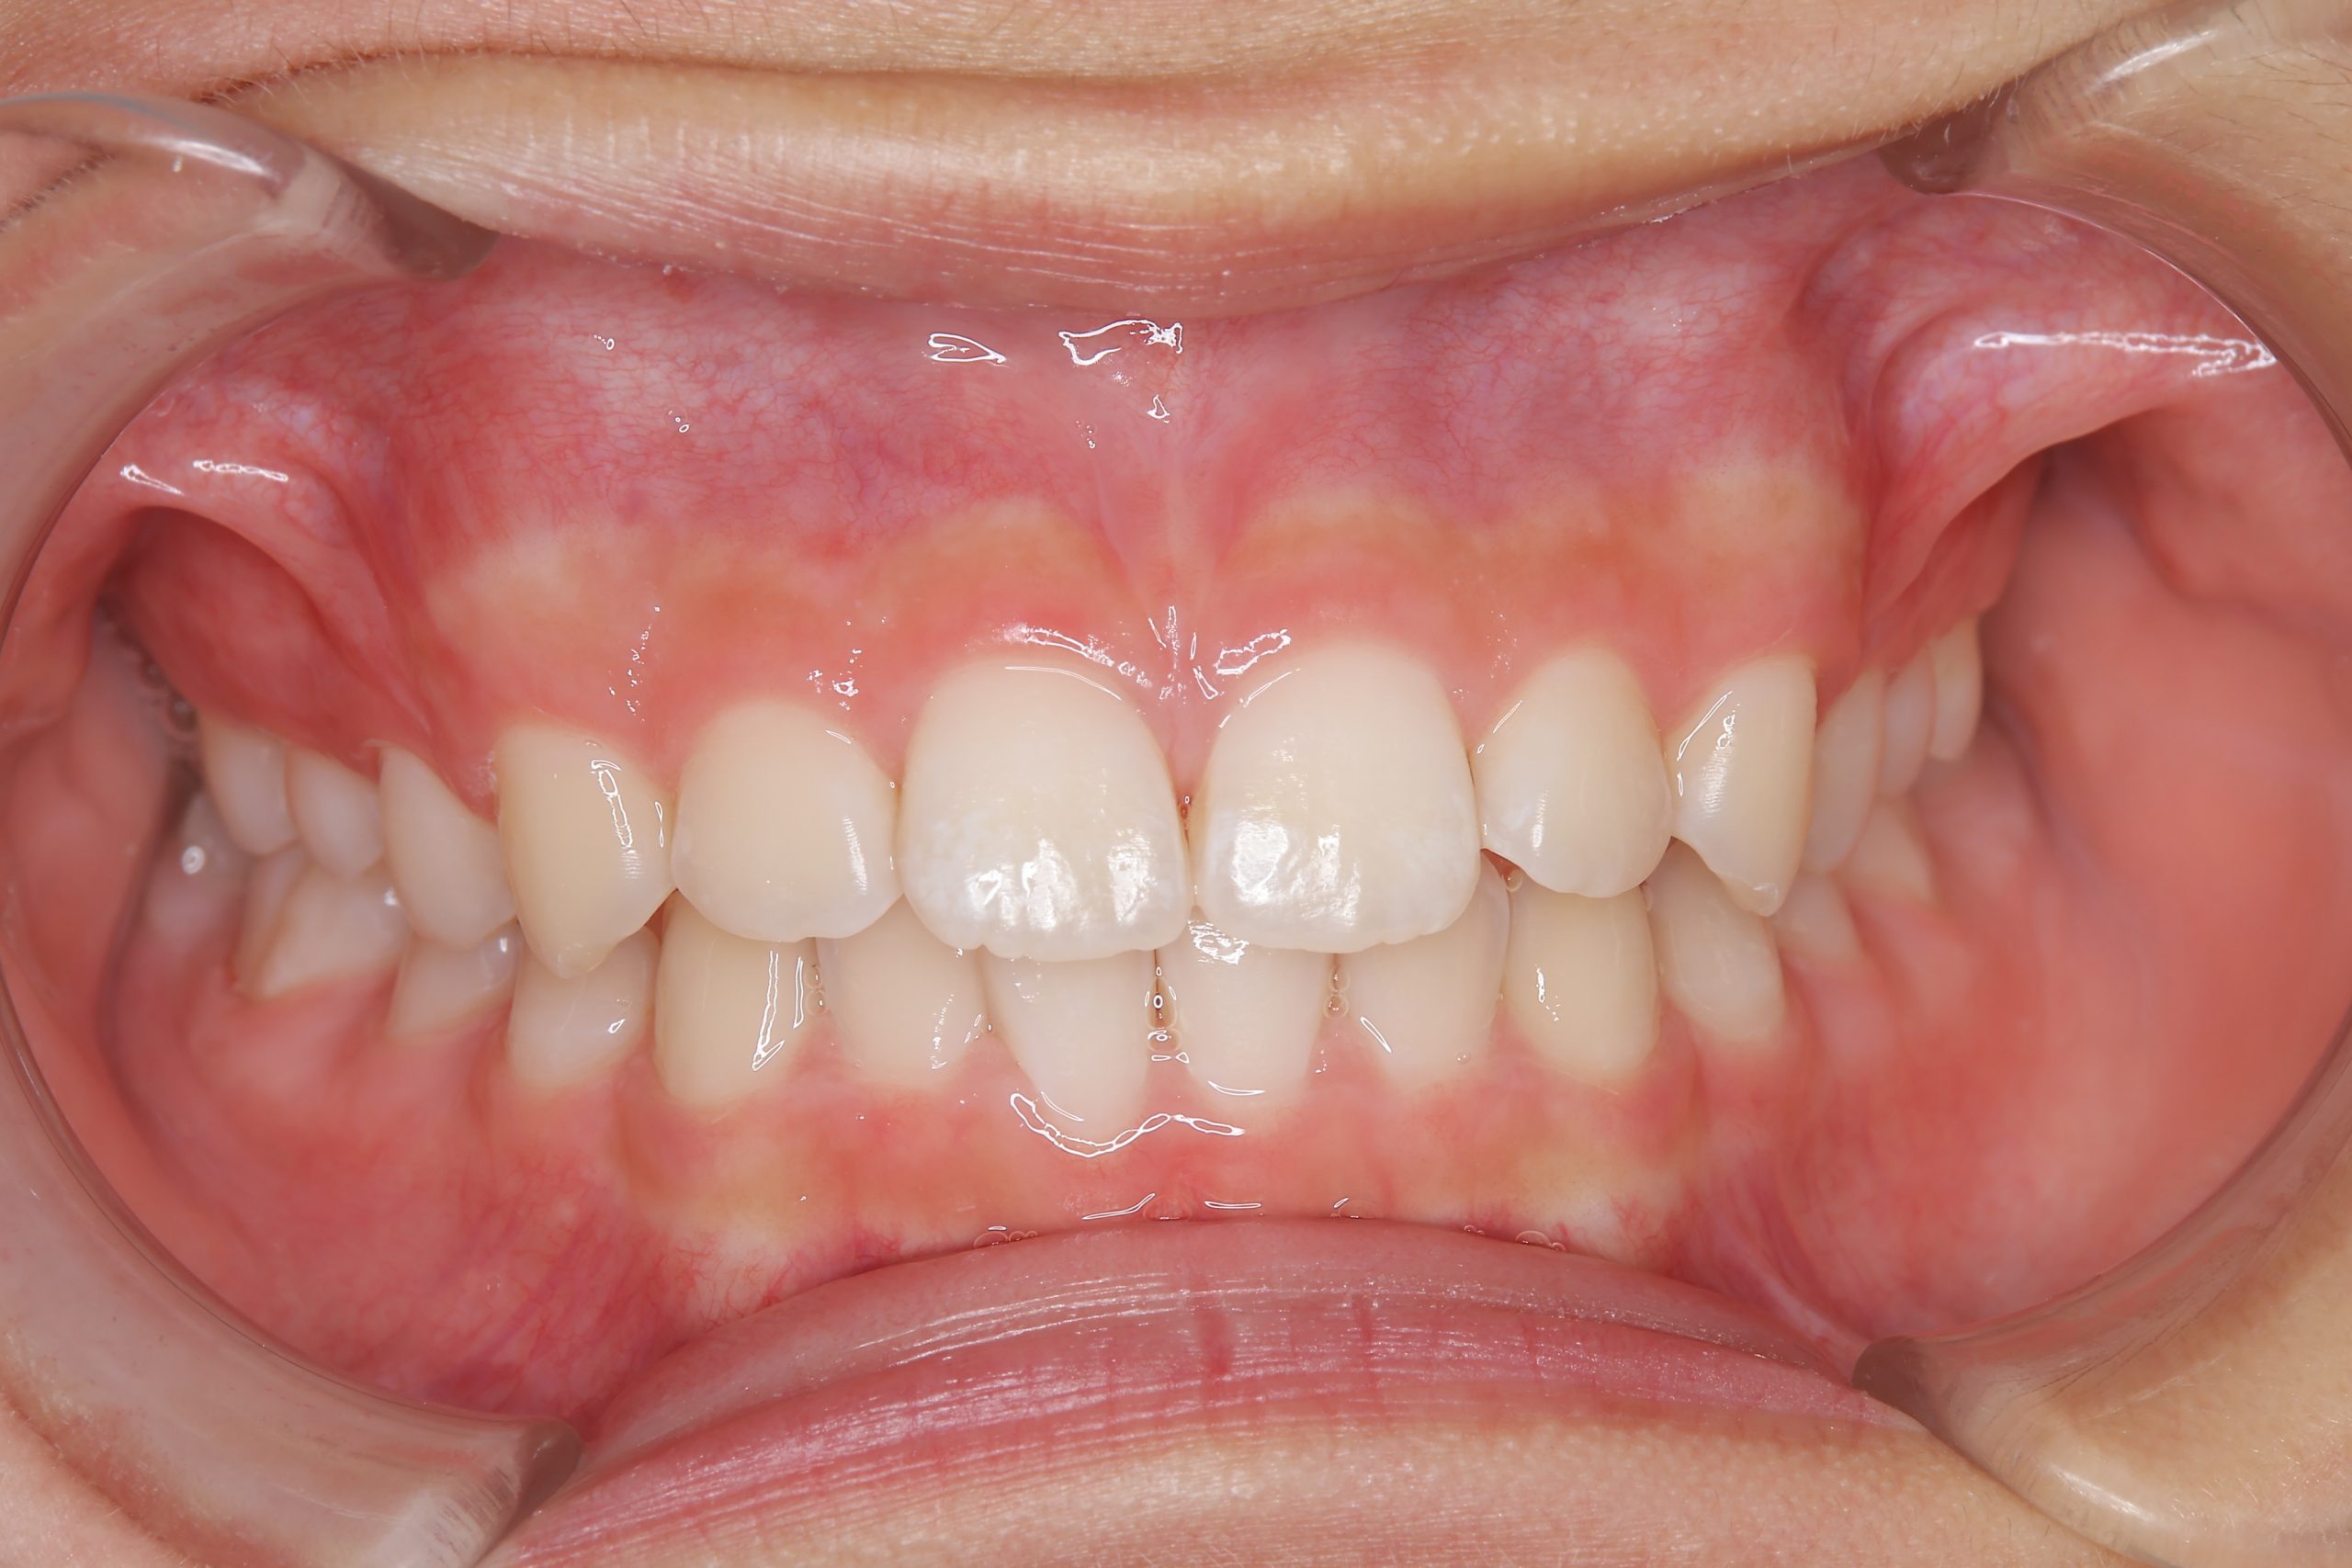

全顎ワイヤー矯正 症例_610 Case

ビフォー

| 主訴 | 前歯の歯並び|歯ぎしり |

| 施術内容 | 小児矯正1期治療 |

| 治癒期間 | 2年4か月間 |

| 費用 | 711,700円(税込) |

| リスク・副作用 | 違和感、不快感、痛み |